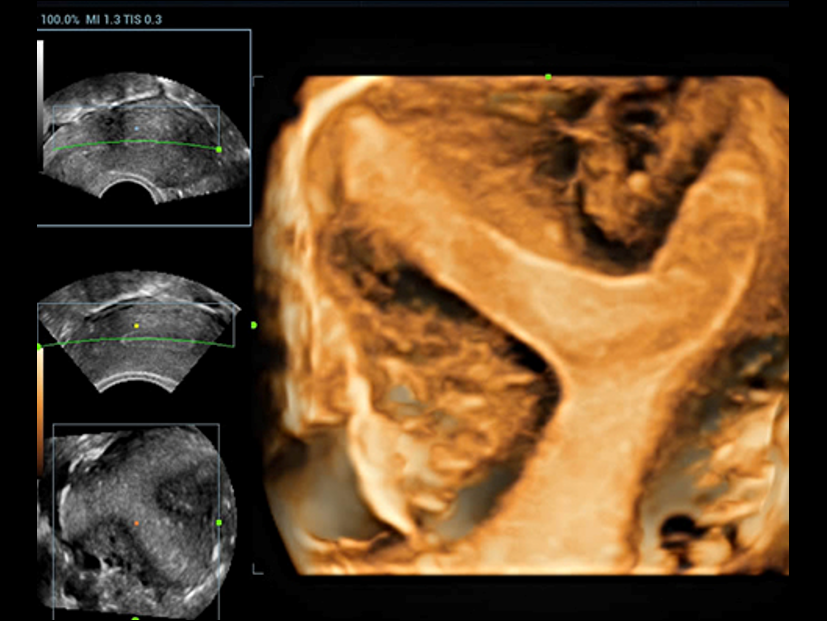

Fin dalla sua fondazione Mindray esplora continuamente nuovi modi per migliorare l'affidabilit├Ā diagnostica. Equipaggiata con la pi├╣ rivoluzionaria tecnologia ZONE Sonography?, la nuova piattaforma ZST+ di Resona 7 porta la qualit├Ā dell'immagine ecografica ad un livello superiore con l'acquisizione per zone e l'elaborazione dei dati canale.

Oltre alla qualit├Ā delle immagini di livello eccellente, Resona 7 migliora anche le capacit├Ā di ricerca clinica il rivoluzionario V Flow per la valutazione emodinamica vascolare, e l'acquisizione piani pi├╣ intelligente dal set di dati 3D per la diagnosi del sistema nervoso centrale fetale. Combinando il pi├╣ intuitivo funzionamento multi-touch basato su gesti e tutte le caratteristiche cliniche essenziali, Resona 7 sta veramente portando nuove tendenze nellŌĆÖinnovazione dellŌĆÖecografia.